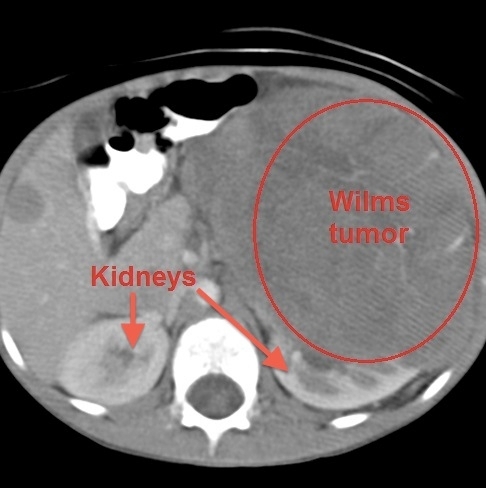

Wilims

Wilms tumor (nephroblastoma) is the most common primary renal neoplasm of childhood. It is usually diagnosed at age 2-5 years and affects a single kidney. The most common presentation is an asymptomatic abdominal mass that is found incidentally by a caretaker or physician. Some patients have abdominal pain, hypertension, hematuria, and fever. Less than 10% of patients have bilateral renal involvement (stage V disease). Although the lungs are the most common site of metastatic spread, children rarely present with pulmonary symptoms.

Abdominal ultrasonography should be the first step in imaging to differentiate Wilms tumor from other causes of abdominal masses. It should be followed by contrast-enhanced computed tomography of the abdomen to evaluate the nature and extent of the mass and of the chest to identify any pulmonary metastases. Treatment includes surgery and chemotherapy with the addition of radiation therapy for high-stage disease. Survival rates are excellent especially if treated in the early stages.

Neuroblastoma can arise anywhere in the sympathetic nervous system but typically involves the adrenal glands and presents as an abdominal mass that crosses the midline with systemic symptoms. This patient's age and asymptomatic abdominal mass are more characteristic of Wilms tumor than neuroblastoma.